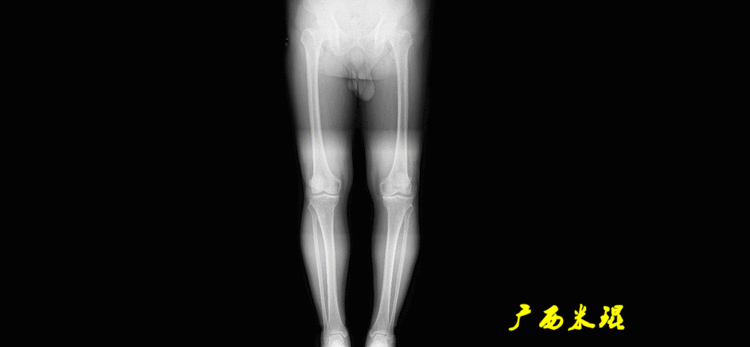

下肢力线及相关角度测量的前提是必须拍摄标准的站立位也就是负重位的下肢全长片。目前这样的照片都是放射科的技师在电脑上拼接出来的,大部分医院的DR都能够做到这一点。

患者直立于摄影架上,后背贴近摄影架,双手自然下垂,膝关节尽量伸直,足部与双肩同宽,要求投照时双髌骨朝正前方,通常患者双足尖应平行向前即可。

提醒一下大家,拍摄过程中应避免下肢的外旋和内旋。如果有一侧肢体短缩时,投照应当用脚垫垫高短缩肢体,使骨盆保持水平,这样下肢短缩测量才精确。如果有肢体旋转畸形时,还是以髌骨朝前为标准,虽然此时双足可能不能保持平行。

二、下肢全长片的基本要求

无论如何,拍摄出来的下肢全长片必须包含髋关节中心、膝关节中心及踝关节中心,否则对临床是无用的。有了一张下肢的全长照片,我们需要确定下肢关节的中心点,通过中心点画出下肢的各种轴线,然后利用轴线与关节线的相交得出各种所需要的角度。